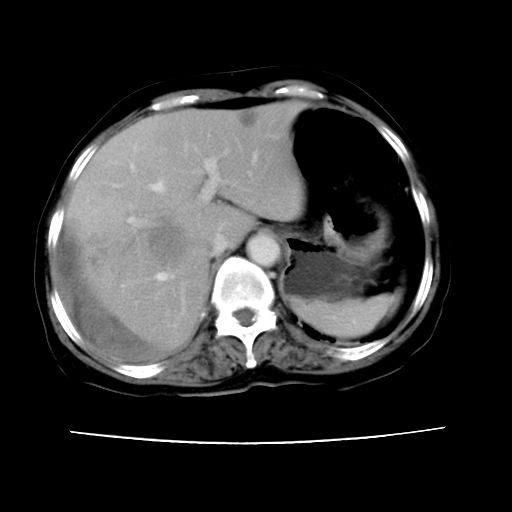

标题: CT16642:男62岁,突发性上腹部疼痛来诊。请讨论!

2008-6-10ct平扫

ct增强

6月份ct片显示肝内巨大混杂密度团块,伴包膜下积液(内含液液平面),增强多无明显强化。只能考虑肝占位病变,并肝内、血膜下血肿。肝ca并出血多见,而肝血管瘤并破裂出血少见。

6月份ct片显示肝内巨大混杂密度团块,伴包膜下积液(内含液液平面),增强多无明显强化。只能考虑肝占位病变,并肝内、包膜下血肿。肝ca并出血多见,而肝血管瘤并破裂出血少见。